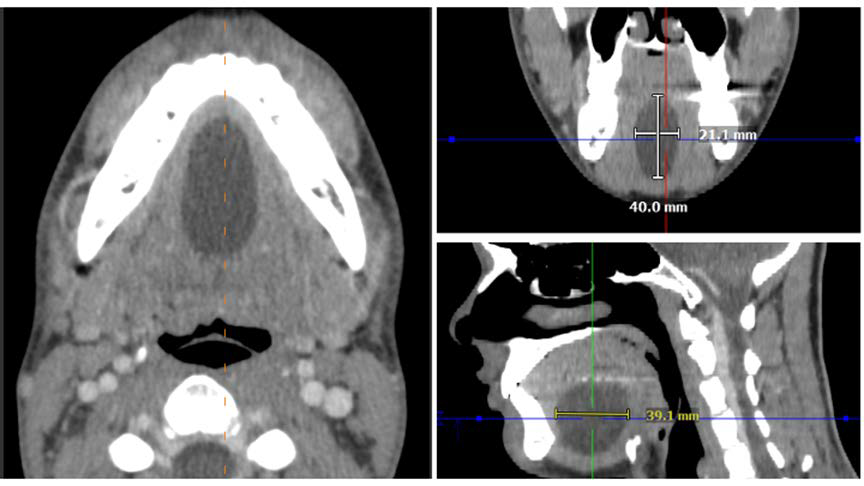

A Different Kind of Marble: Sublingual Epidermoid Cyst with the "Sack of Marbles" Sign

Sara Salehi, Tubo Shi, Alex A. Nagelschneider, Bradley J. Erickson

1-11